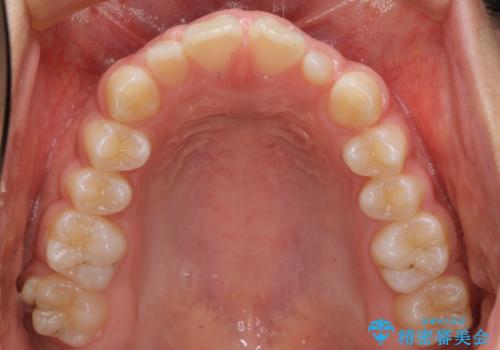

前歯のすきま 矯正治療とセラミックで小さな歯を形良く

- 前歯のすきまを気にして来院。

左上の2番が生まれつき小さく、スペースが余っていました。

右上の2番もやや小さめでしたが、相談の上、左上2番のみセラミックで形を整えることとしました。

そのほかの隙間はマウスピース矯正で閉じることにしました。

当初はワイヤー矯正を希望されていましたが、右上7番の頬側に咬頭があり、ブラケットを貼ることが難しいため、こちらからマウスピース矯正をお勧めしました。